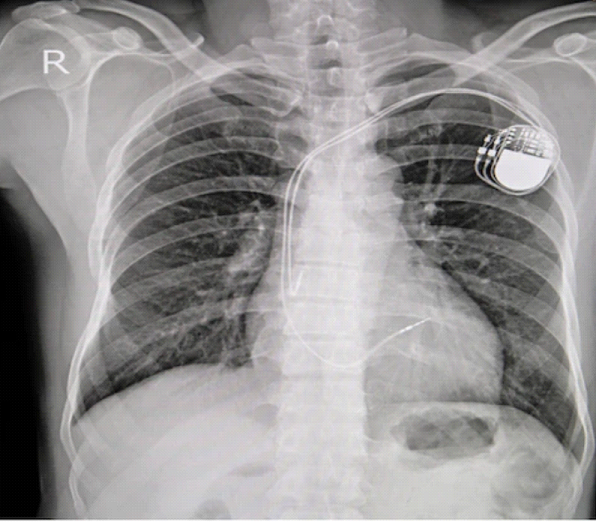

Après avoir contrôlé le bon fonctionnement et le bon positionnement des sondes, celle-ci sont connectées au connecteur du générateur. Le boitier est enfin positionné dans la loge réalisée. Il est parfois fixé pour éviter qu’il ne se déplace. Enfin, la loge est refermée souvent en 2 ou 3 plans par des fils résorbables et/ou des agrafes. Un pansement compressif est souvent mis en place pendant quelques heures pour éviter la survenue d’un hématome de loge. Par la suite, une radiographie de thorax est réalisée le lendemain de l’intervention pour vérifier l’absence de déplacement de sonde. Le patient sort généralement à J1 puis des soins locaux sont réalisés à domicile pendant une dizaine de jour. Le patient doit sortir avec son carnet de PM et son boitier de télécardiologie.